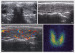

Abbildung 12a-b: Karzinom Karzinom. a: Querschnitt durch den linken Schilddrüsenlappen. b: Der unscharf begrenzte echoarme Knoten zeigt dopplersonographisch eine deutlich gesteigerte Perfusion. Histologischer Befund: Medulläres Schilddrüsenkarzinom. |